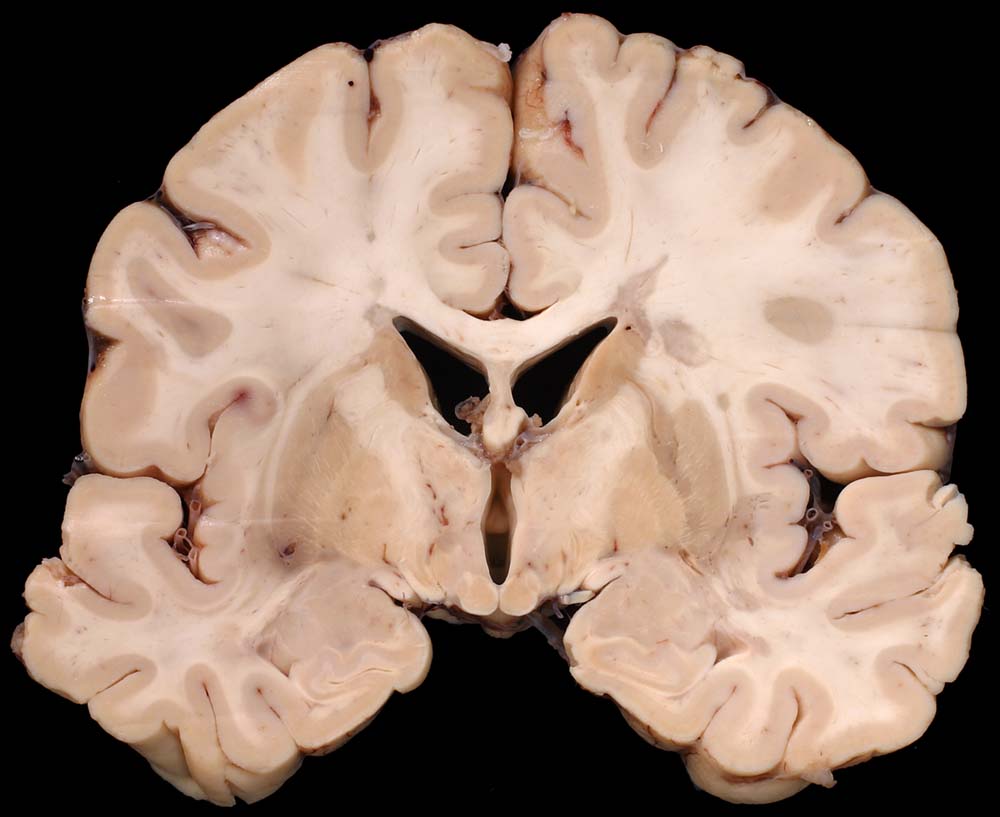

PathoPic – image database / PathoPic ID 8793 - Periventrikulär betonte Entmarkungsherde bei multipler Sklerose

Periventrikulär betonte Entmarkungsherde bei multipler Sklerose

Systemerkrankung/Immunpathologie

Hirn parietal

Nervensystem

Multiple Sklerose (Erstdiagnose vor 30 Jahren) mit spastischer Paraparese und neurogener Blasenmotorikstörung.

Makroskopie